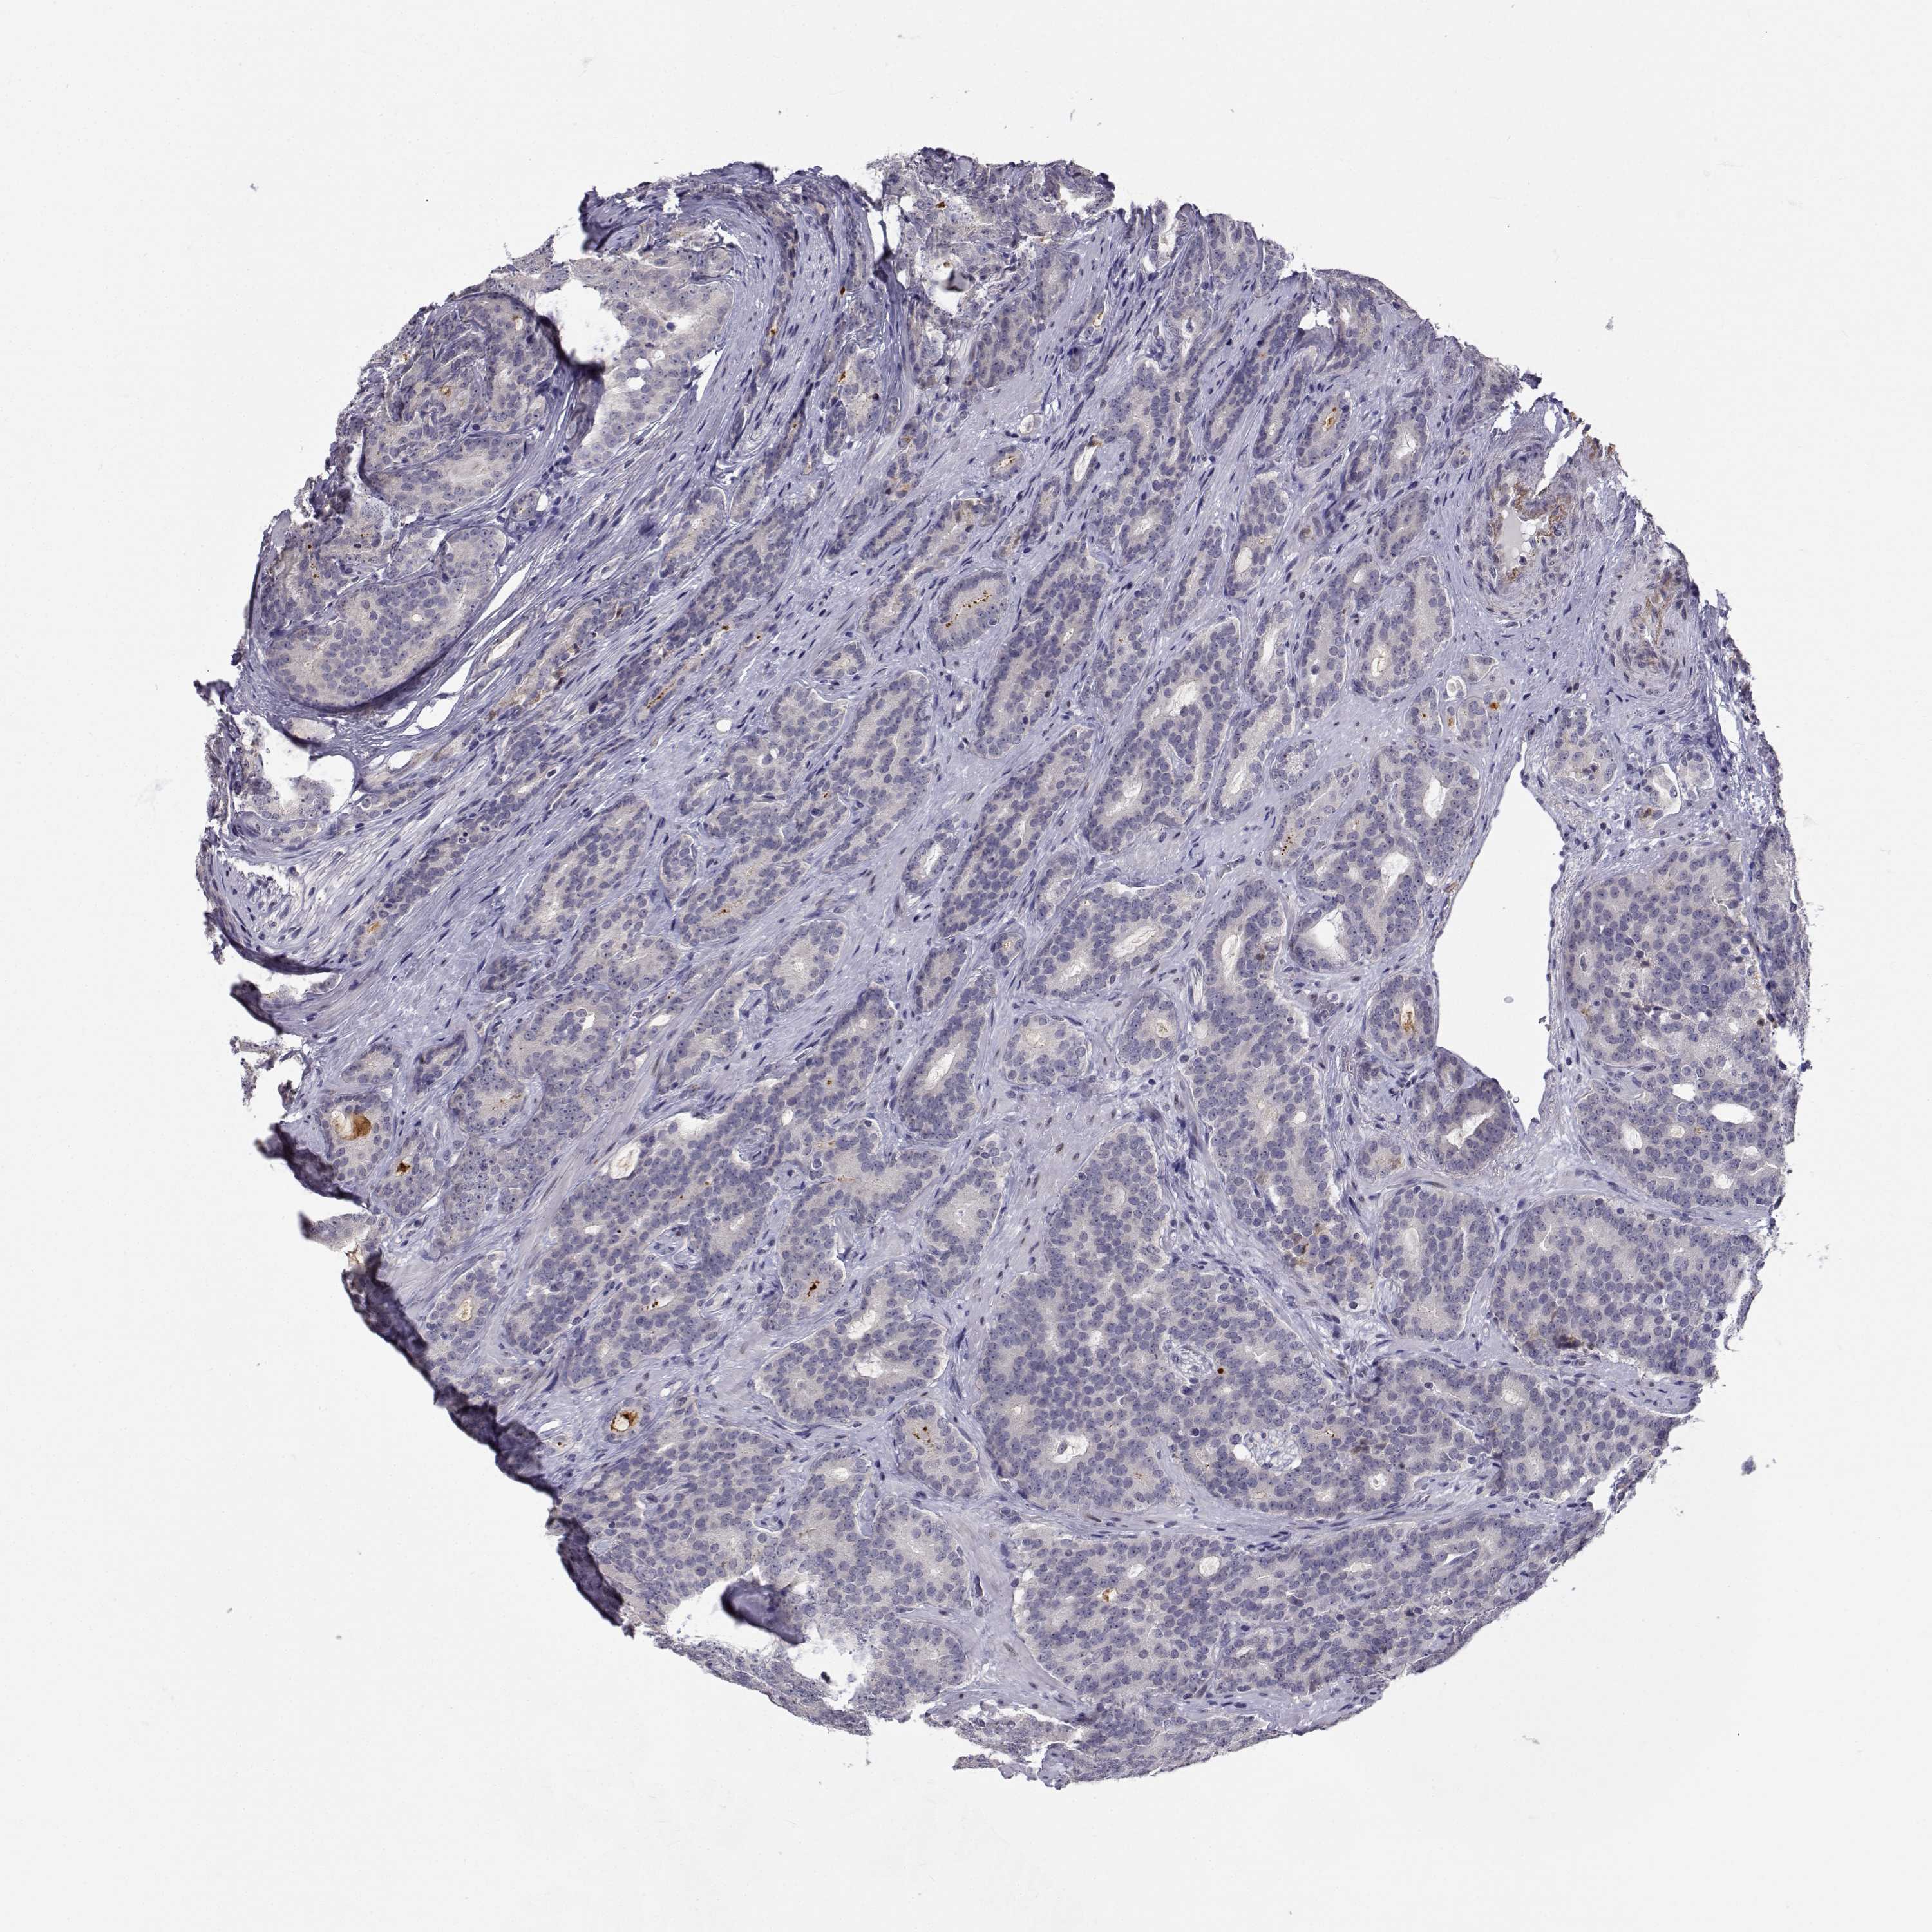

PROSTATE CANCER - Protein expressioni

A mouse-over function shows sample information and annotation data. Click on an image to view it in a full screen mode. Samples can be filtered based on level of antibody staining by selecting one or several of the following categories: high, medium, low and not detected. The assay and annotation is described here.

Antibody stainingi

Antibody staining in the annotated cell types in the current human tissue is reported as not detected, low, medium, or high, based on conventional immunohistochemistry profiling in selected tissues. This score is based on the combination of the staining intensity and fraction of stained cells.

Each image is clickable and will lead to virtual microscopy that enables deeper exploration of all samples and also displays staining intensity scores, fraction scores and subcellular localization as well as patient and tissue information for each sample.

Antibody CAB016249

Adenocarcinoma, NOS